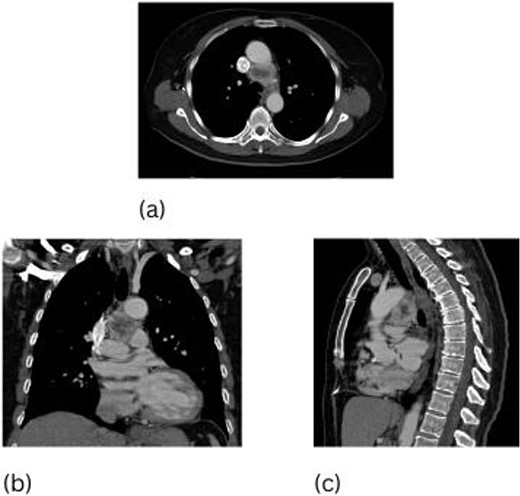

A 66-year-old woman presented with generalized fatigue and chronic cough. A CT scan of her chest revealed a 3.5 cm paraganglioma in the AP window as well as a 1.6 cm left adrenal mass (Fig. 3). Mediastinal paraganglioma resection was performed via median sternotomy with 67 min of CPB. The mass in this patient was densely attached to the ascending aorta. Sharp dissection was carried out circumferentially around the ascending aorta and then superiorly to the arch. The inferior aspect of paraganglioma was carefully mobilized from the main pulmonary and right pulmonary arteries until mass was completely excised. Paraganglioma measured 3.5 × 3.0 × 2.0 cm with diffuse immunoreactivity for chromogranin, synaptophysin, CD56, S-100, and vimentin. Patient recovered well from her surgeries with postoperative annual imaging revealing no recurrence for 5 years.

CT scan of the chest, 3.5 cm paraganglioma with necrotic center (a–c).